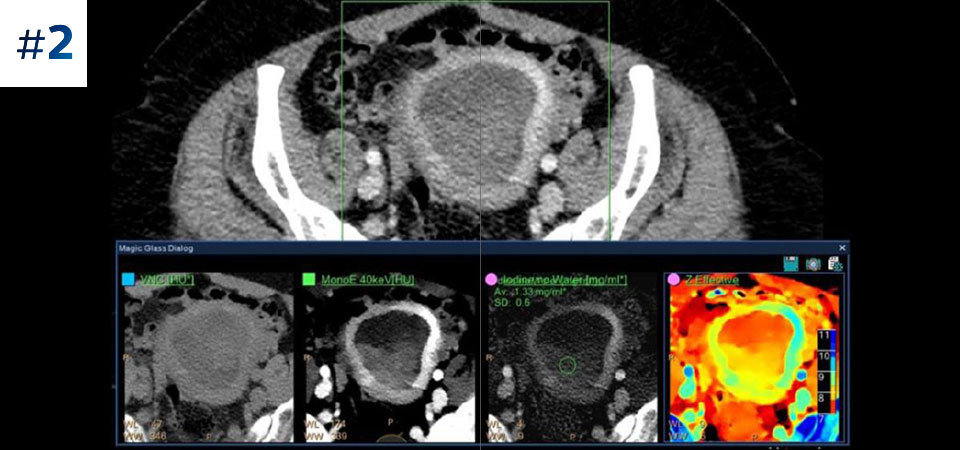

With detector-based spectral, you acquire multiple layers of data—conventional and spectral—within a single exposure and without special scan modes for improved tissue characterization and visualization.

Reduced follow-up exams Improved tissue characterization and visualization may reduce the need for follow-up scanning for sub-optimal exams and incidental findings.

Can you solve the mystery diagnosis using spectral?

Go beyond conventional CT. See how layers of spectral-detector results can enhance your diagnostic confidence.